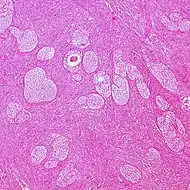

| Adult granulosa cell tumor | 1% | Almost 100% | Small, bland, cuboidal to polygonal cells in various patterns.[9] | .jpg.webp) | |